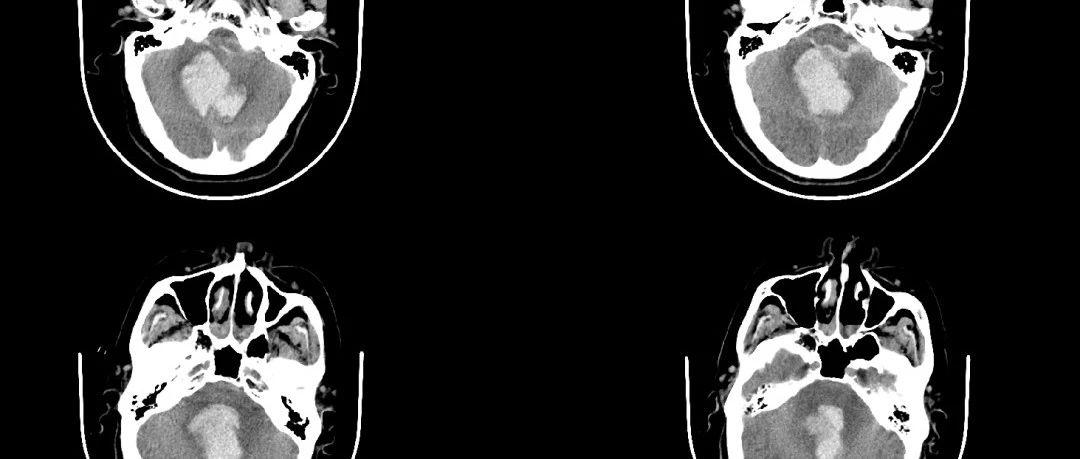

病例1

患者因“突發(fā)意識不清2小時”入院。行急診CT檢查提示:“小腦出血并破入腦室”,出血量達45毫升,病情嚴重,神經(jīng)外科團隊馬上制定手術方案,行急診顯微鏡下小腦血腫清除術,手術過程順利,術后復查血腫完全清除,經(jīng)過康復和護理,患者神志漸清,目前已順利出院。